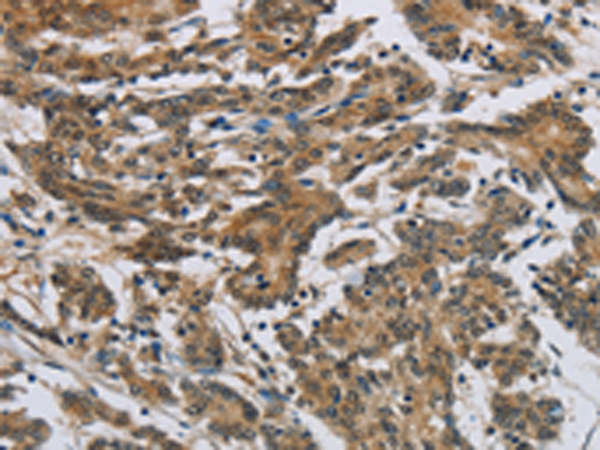

分类: 科研抗体货号: P11853别名: SYNII; SYNIIa; SYNIIb应用: WB,IHC反应种属: Human, Mouse, Rat